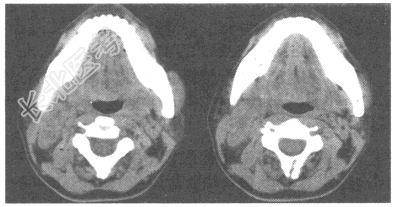

- 单项选择题女性,28岁。2个月前发现右颈有一肿块, 无压痛,可移动。肿块缓慢增大。患者有盗汗、红细胞沉降率加快。体检: 右侧胸锁乳突肌后缘可触及串状肿大淋巴结,直径0.7~1.5cm。CT图像如下, 可诊断为

A、颈淋巴结结核

B、淋巴瘤

C、神经鞘瘤

D、转移瘤

E、淋巴管瘤